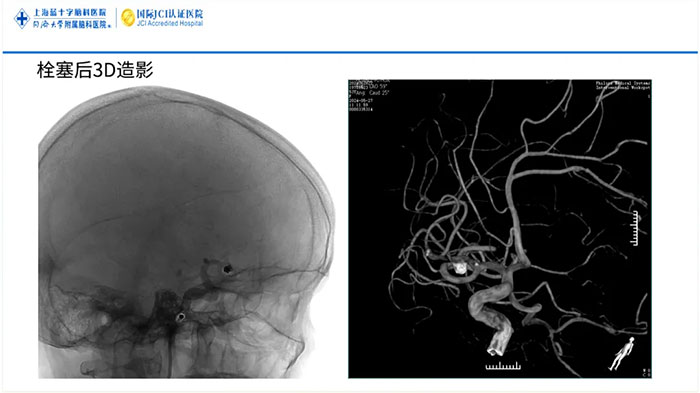

常規(guī)的介入手術(shù)治療腦血管狹窄需要在術(shù)中進(jìn)行多次交換,如導(dǎo)絲交換、球囊交換以及支架微導(dǎo)管交換,手術(shù)步驟相對(duì)較多,手術(shù)風(fēng)險(xiǎn)也相對(duì)增加。而“零交換”技術(shù),通過(guò)使用新材料輸送型球囊擴(kuò)張導(dǎo)管,可以免去手術(shù)步驟中的導(dǎo)絲交換、球囊交換以及支架微導(dǎo)管交換步驟,在球囊擴(kuò)張后直接釋放支架,簡(jiǎn)化操作步驟,提高手術(shù)的安全性,縮短手術(shù)時(shí)間,為患者帶來(lái)了福音。

上海藍(lán)十字腦科醫(yī)院腦血管病科神經(jīng)介入團(tuán)隊(duì)已開(kāi)展了十余例“零交換”技術(shù)治療顱內(nèi)動(dòng)脈粥樣硬化性狹窄的手術(shù),涉及大腦中動(dòng)脈、大腦前動(dòng)脈、大腦后動(dòng)脈、基底動(dòng)脈、頸內(nèi)動(dòng)脈顱內(nèi)段、椎動(dòng)脈V4段等顱內(nèi)動(dòng)脈部位,均為高難度四級(jí)神經(jīng)介入手術(shù)。